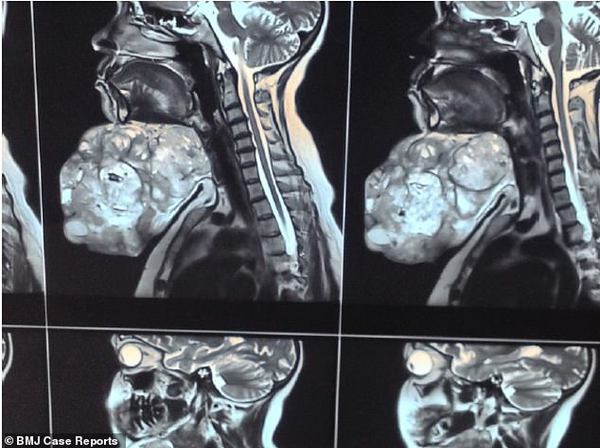

【环球网综合报道】据英国《每日邮报》12月7日报道,18年间,印度一位47岁妇女在下巴处长了一颗近9斤重的肿瘤,现已通过手术切除。

术前术后对比图展示了,外科医生为一名妇女切除下巴的巨大肿瘤后,该妇女发生的巨大变化。这位47岁的妇女告诉医生,这颗奇怪的肿瘤长了近20年。

印度北方邦的医生表示,一般新生儿的体重只有6斤左右,近9斤重的肿瘤着实让人吃惊。他们对这个病例十分感兴趣,于是决定将其发表在著名刊物《英国医学病理报告杂志》上。阿拉哈巴德Moti Lal Nehru医学院的研究小组称,这种大型多形性腺瘤在医学文献中十分罕见。这位妇女的病例报告中,外科主治医生Ashutosh Rai写道:“即使是在现代生活中,出现如此大型的肿瘤还是十分令人吃惊的。”

他们透露,因为这位妇女害怕进行激烈的手术,所以她逃避了18年才来就医。最后,这位妇女决定在家乡阿拉哈巴德的医院进行治疗。她表示,这些年来这颗肿瘤一直缓慢生长,但过去的这两年间却突然急速增长。

虽然肿瘤目前已经切除,但仍不知道渗出的液体是否会产生气味,也不知道颜色为何。外科医生没有透露任何手术细节,但他们表示,术后5个月内病人恢复良好,没有任何并发症发生。

多形性腺瘤又称混合瘤,是生长在涎腺的良性肿瘤。数据显示,这是最常见的涎腺肿瘤,占所有涎腺肿瘤的70%。但目前尚不清楚良性涎腺肿瘤的发病原因。(实习编译:张蓝艳 审稿:李宗泽)